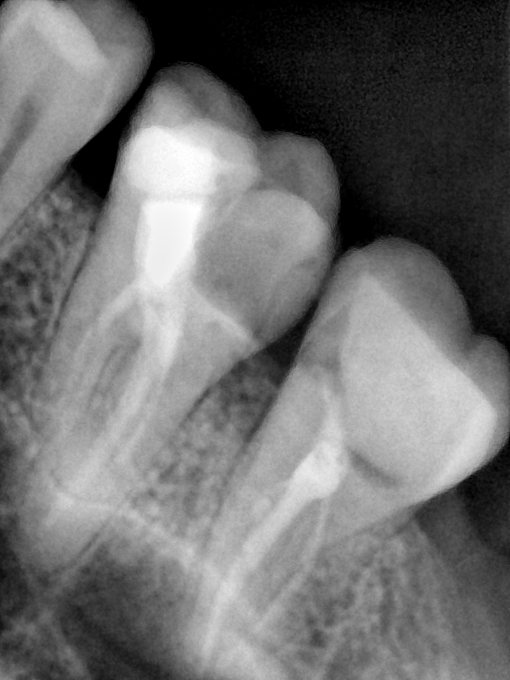

CR/DR 牙齿分割阶段记录

当前进展

- 完成了 CR/DR 牙齿相关分割训练

- 当前结果已经达到阶段预期,但仍有细节问题需要继续处理

相关测试

遇到的问题

- 训练过程中出现过 mask 下移问题

- 部分结果会出现 box 填充异常

- mask 边缘仍然有比较明显的锯齿感

参考

第二版算法问题测试